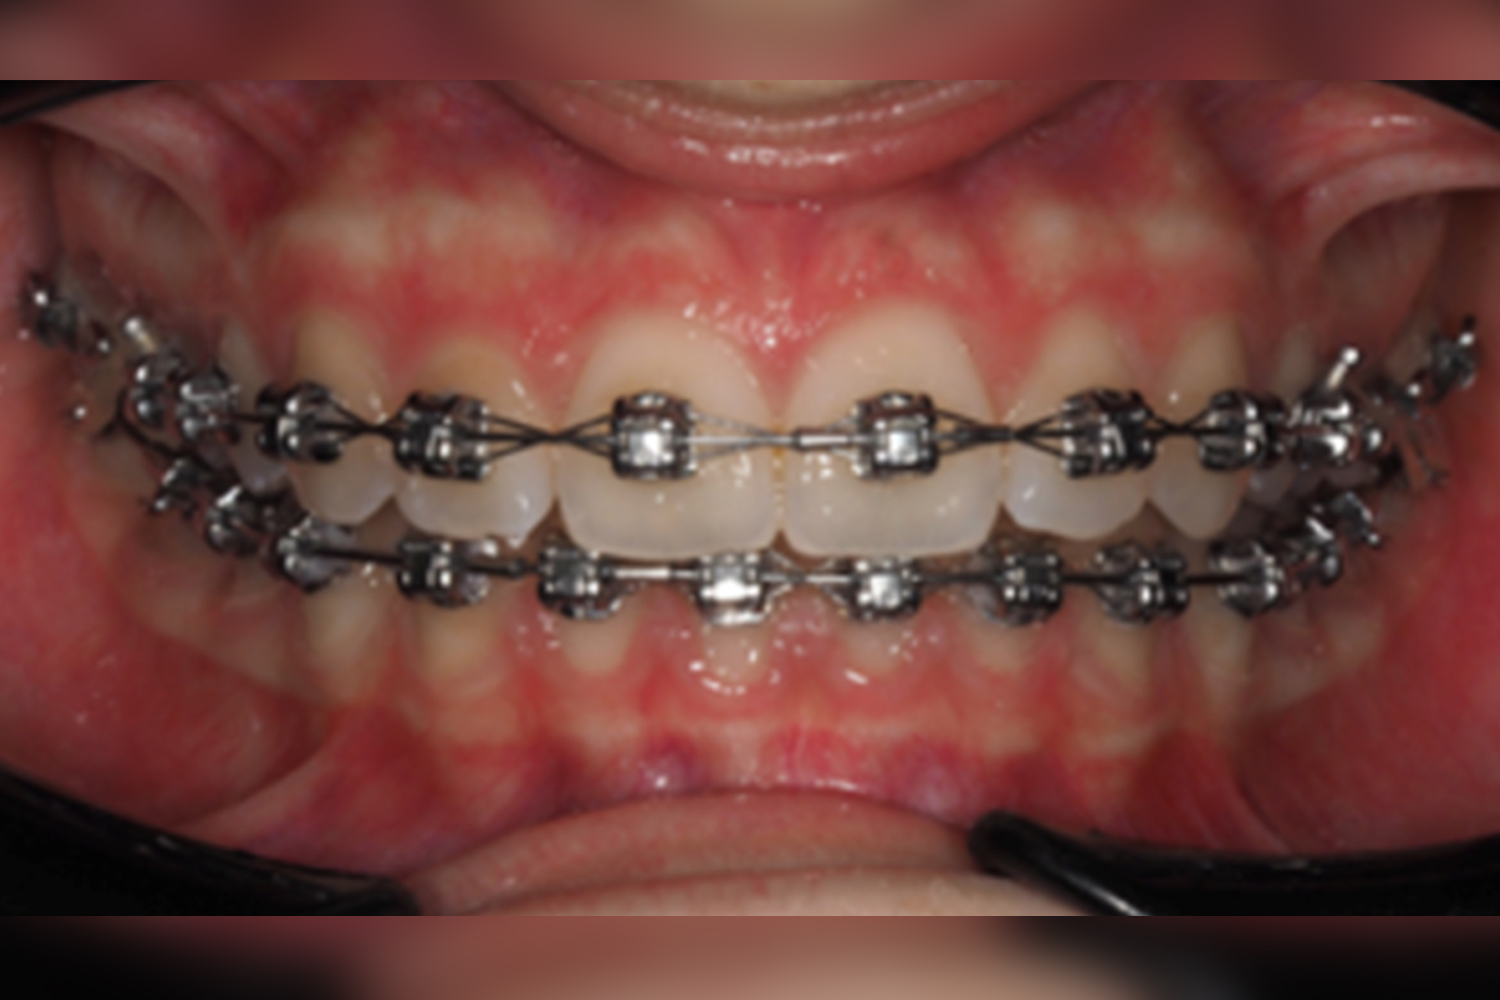

Pano reposition visit:

While 6 weeks with 18×275 CuNiTi upper and lower archwire, a panoramic reposition visit wasplanned, and LL1 was replaced for second-order correction. The LL8 was extracted at this momentdue to patient´s discomfort as the others were planned to be extracted after bracket debonding.

March 2023

May 2023